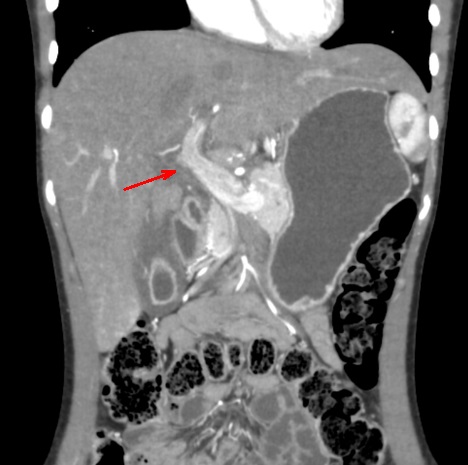

Hepatite aigue : Aspect de

hypodense region perioportale et peri hillaire du

foie ( >5mm ) . Image de hypodense de la parenchyme

du foie . Lymphadenopathie hillare dans ce cas est

en bien se voyait . Image radiologique du foie

en coupe TDM axiale . |

|

Aspect hypodense du

parenchyme du foie dansd hepatite aigue . Le

foie est en moins densite que la rate . Et image de

hypodense region periportale et image de

adenopâthie hileire du foie . |